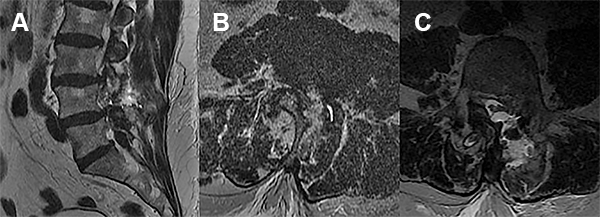

Se decidió internación para valoración clínica y por imágenes. Por resonancia se evidenció colección de LCR en el sitio de la reparación dural (fig. 1).

Figura 1